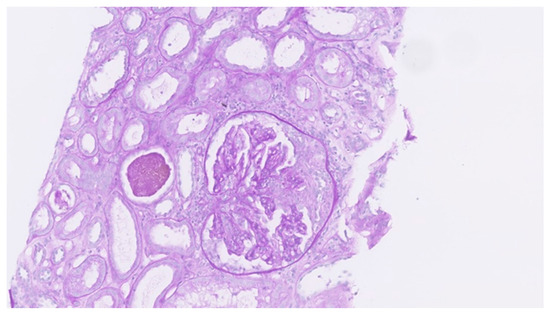

Uncommon Presentation of Granulomatosis with Polyangiitis Mimicking Metastatic Lung Cancer